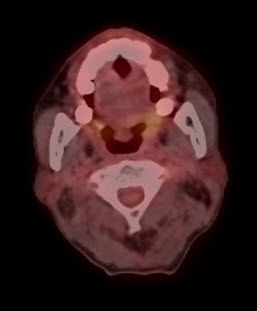

Trước điều trị: hình PET/CT thấy khối u thanh quản (mũi tên vàng) và hạch cổ trái (mũi tên xanh) tăng hấp thu FDG mạnh. SUV u thanh quản = 5,31; SUV hạch cổ = 4,87

Sau hóa xạ trị: u và hạch biến mất, trên hình PET/CT không thấy các tổn thương này nữa.

Hình 1. Bệnh nhân Lê B. L., nam, 66 tuổi. Chẩn đoán: Ung thư thanh quản (ung thư biểu mô tế bào vảy) di căn hạch cổ. Bệnh nhân được chụp PET/CT để đánh giá giai đoạn trước điều trị và mô phỏng lập kế hoạch xạ trị; sau khi được điều trị hóa chất và xạ trị (IMRT) bệnh nhân được chụp lại PET/CT để đánh giá kết quả điều trị. Kết quả cho thấy bệnh đáp ứng hoàn toàn.